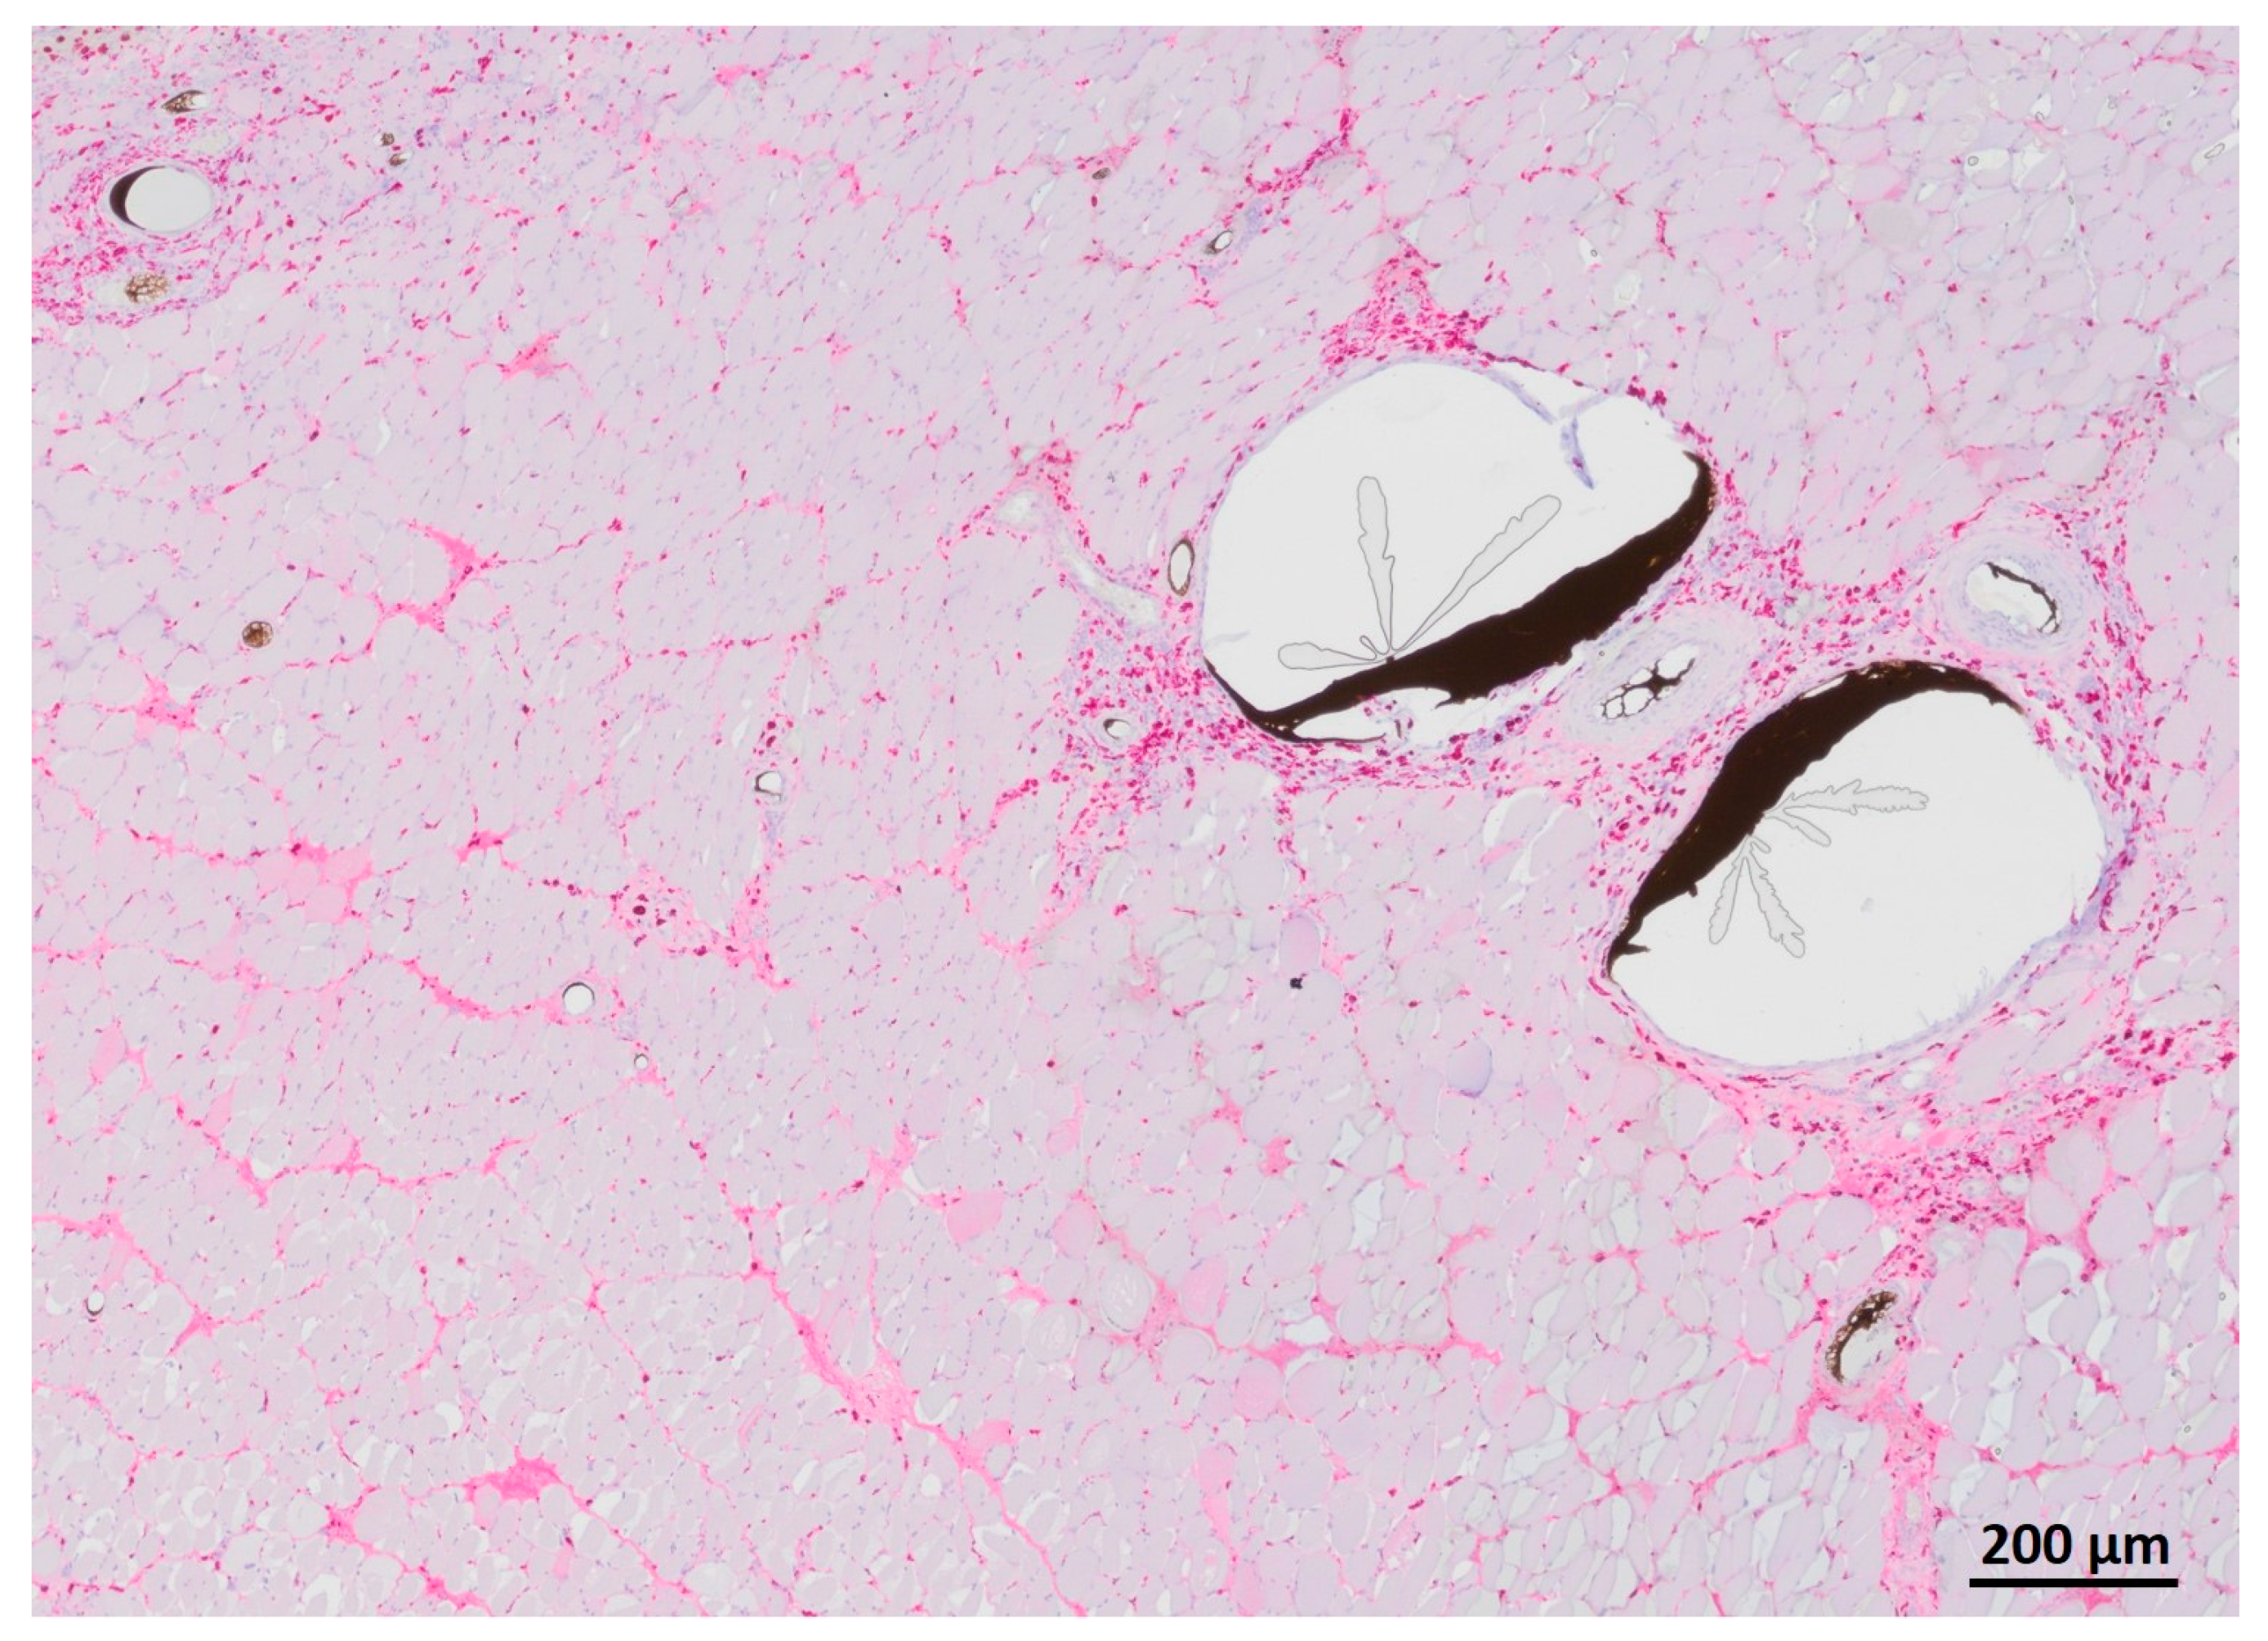

3.5. Myofiber Morphology and Macrophage Invasion